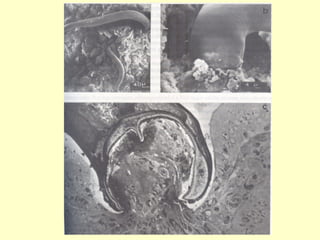

•   Causador – Ascaris lumbricoides ( lombriga)

•   Ciclo monóxeno – Homem (HD)

•   “oral-fecal”

Ascaridíase • Causador – Ascaris lumbricoides ( lombriga) • Ciclo monóxeno – Homem (HD) • “oral-fecal” • Considerada a parasitose mais prevalente no mundo